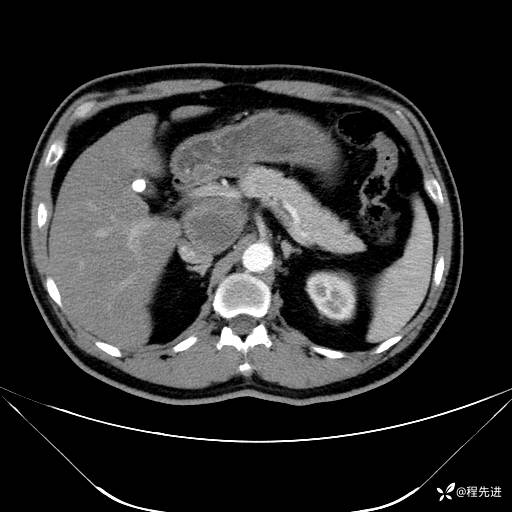

【腹盆】特别精彩病例|发现腹膜后肿物1月余

主诉:发现腹膜后肿物1月余

现病史:患者1月余前查体,行超声检查提示:后腹膜囊实性肿块;慢性胆囊炎伴胆囊内结石;无腹痛腹胀,不伴腹泻发热等;偶感腰背部酸痛。

CT平扫+增强: